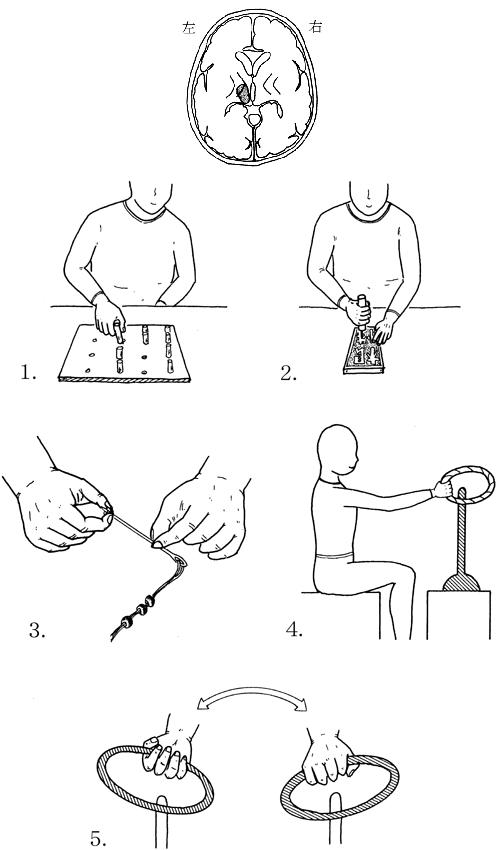

53歳の男性。脳出血による右片麻痺。ブルンストローム法ステージは上肢IV・手指IIIでやや痙縮が強い。麻痺側でコップの水を飲んでもらったところ図1のような反応がみられた。このような反応を軽減するための訓練として図2のような動作を行う際に注意すべき点で適切でないのはどれか。

1

麻痺側上肢の運動に抵抗をかける。

2

麻痺側肩関節は外旋位に保持する。

3

非麻痺側上肢をリラックスさせる。

4

麻痺側肩甲帯の前方突出を保持する。

5

頸部と体幹は軽度屈曲を保持する。